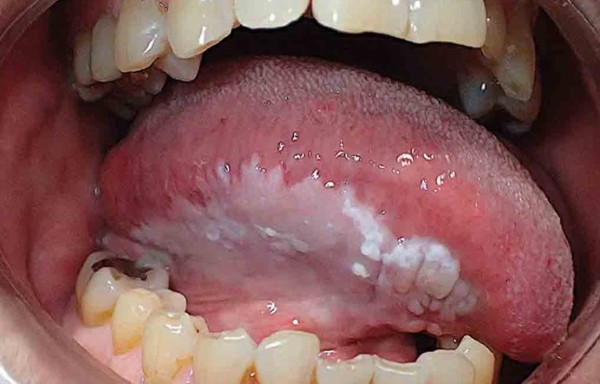

Nấm Candida giới thiệu những biểu hiện như miệng trắng hoặc đốm trắng, vết loét, gây khó chịu, đặc biệt ở người có hệ miễn dịch suy yếu hoặc dùng thuốc kháng sinh kéo dài.

Triệu chứng nghi ngờ ung thư niêm mạc miệng

Một niêm mạc miệng khỏe mạnh có màu hồng đều, độ ẩm bình thường, bề mặt sáng bóng, đàn hồi tốt, không có vết loét hoặc mảng bám bất thường. Khi quan sát kỹ, chúng ta dễ dàng phát hiện sự thay đổi về màu sắc như trắng bệt, đỏ rực, hoặc xuất hiện các nốt mẩn đỏ, mảng trắng hay đốm đen.

Hàng ngày, bạn nên dành chút thời gian kiểm tra khoang miệng, chú ý tới các dấu hiệu như đau rát, sưng tấy, lõm hoặc loét kéo dài trên bề mặt niêm mạc. Màng trắng hoặc các vết loét không tự lành sau vài ngày có thể là dấu hiệu cảnh báo cần đi khám bác sĩ nha khoa để xác định chính xác nguyên nhân.

Thay đổi màu sắc niêm mạc, xuất hiện các mảng trắng, đỏ đậm hoặc có mùi hôi kéo dài đều là dấu hiệu cảnh báo cần thiết để kiểm tra và phát hiện sớm ung thư hoặc các bệnh lý khác.